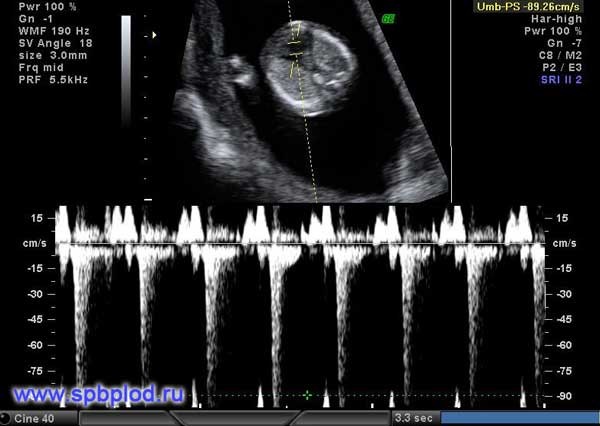

Помимо измерения толщины воротникового пространства и оценки носовой кости, предложено еще несколько маркеров: оценка кровотока через трикуспидальный клапан сердца и через венозный проток, а так же измерение лицевого угла плода. Оценка данных маркеров требует от врача высокой квалификации, и возможна только после получения международной сертификации по каждому маркеру.

Обычно кровь в сосудах плода течет в одном направлении: от сердца к периферическим сосудам. При наличии хромосомной патологии у плода или пороков сердца направление тока крови может изменяться, и в некоторые фазы сердечного цикла кровь начинает течь обратно к сердцу.

Обратный кровоток в венозном протоке плода в 12 недель беременности

Регистрация кровотока через трикуспидальный клапан сердца и через венозный проток (этот небольшой сосуд есть только у плодов, в периоде новорожденности кровоток в нем прекращается, и он закрывается) позволяет выявить до 65% плодов с болезнью Дауна. У 1-3% нормальных плодов мы также можем увидеть обратный кровоток в венозном протоке или через трикуспидальный клапан, поэтому эти признаки должны оцениваться в комплексе с другими данными ультразвукового исследования.